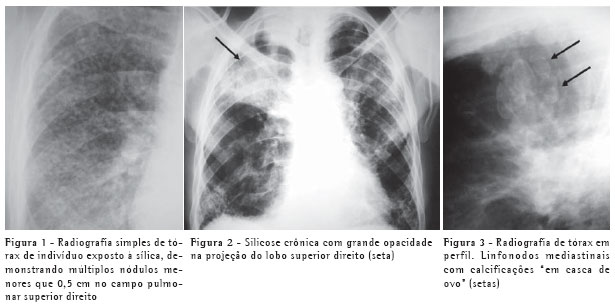

O padrão característico na radiografia é o de pequenos nódulos pulmonares circunscritos, menores que 0,5 cm, geralmente acometendo os campos pulmonares superiores, especialmente as regiões posteriores (Figura 1). Estes nódulos, com o passar dos anos, tendem à coalescência, com formação de grandes opacidades, maiores que 1 cm, o que é conhecido como silicose complicada (Figura 2). Estas podem estar acompanhadas de fibrose pulmonar (fibrose maciça progressiva), com redução volumétrica lobar, distorção arquitetural, retração hilar e fissural e aumento irregular dos espaços aéreos adjacentes.(3)

Podem também ser evidenciadas calcificações em linfonodos hilares ou mediastinais, por vezes periféricas, com padrão de "casca de ovo" (Figura 3).